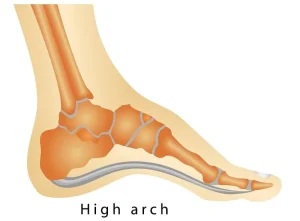

قوس بلند کف پا یا High Arches یک ناهنجاری شایع پا است که در آن قوس طولی کف پا بیش از حد طبیعی است. این مشکل باعث توزیع فشار غیر یکنواخت روی پا، درد مزمن، خستگی سریع و آسیبهای مفصلی میشود.

ساختار کف پا و نقش قوس طولی

پا از سه قوس اصلی تشکیل شده است:

- قوس طولی داخلی: از پاشنه تا انگشتان بزرگ، مهمترین قوس برای توزیع وزن است.

- قوس طولی خارجی: کمک به تعادل و ثبات در هنگام راه رفتن و ایستادن.

- قوس عرضی: زیر پنجه، برای تحمل وزن و انعطاف پا در حرکات پیچشی.

در حالت طبیعی، قوس طولی داخلی فشار را بین پاشنه و پنجه توزیع میکند. در قوس بلند کف پا، این قوس بیش از حد برجسته است و باعث میشود وزن بدن به نقاط محدودی مانند پاشنه و پنجه منتقل شود، که منجر به درد، التهاب و خستگی سریع میشود.